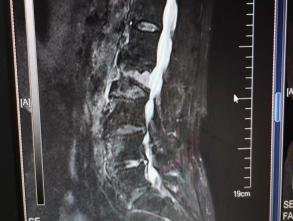

12月17日,贵州航天医院第88次晨读会由我院骨一科主任、副主任医师陈明勇作学术交流,他以“肱骨近端骨折并肩关节脱位的手术治疗”为题,全面讲解了该损伤的手术策略、术中血供保护理念及内侧支撑重建技术等内容,并通过多个典型病例图文资料分享了从损伤机制分析、手术步骤实施到术后随访评估的完整过程与关键细节,为临床处理此类复杂骨折提供了较为全面的技术参考,有助于在手术规划中结合个体情况开展针对性治疗。 贵州航天医院 骨科专家简介 陈明勇 骨一科主任,副主任医师 临床擅长:从事创伤骨科工作约20年,对骨缺损、骨不连、骨肿瘤、肢体畸形等的肢体矫形重建及功能重建,慢性化脓性骨髓炎的根治治疗、糖尿病足的保肢治疗、快速康复理念(ERAS)下的老年骨折的诊治,四肢复杂骨折的诊治,四肢骨折等微创手术治疗具有丰富的临床经验。 2004年毕业于遵义医学院临床专业,曾在中国人民解放军总医院、广西医科大学第一附属医院、上海第六人民医院骨科进修。中国中西医结合学会骨伤科专业委员会横向骨搬移治疗糖尿病足及微血管网再生学组首届委员,遵义市医学会创伤分会常务委员。 瞿 晖 骨科党支部书记,骨二科主任,副主任医师 临床擅长:对骨科的常见病、关节外科、脊柱外科及运动医学疾病的诊治具有丰富的临床经验,熟练掌握骨科手术操作技术。 毕业于遵义医学院临床医学系,2005年前往广州中山大学第一附院骨显微医学部进修学习,2011年前往成都华西医院进修学习,并多次在省内外学习骨科相关知识,是中华医学会骨科分会会员。 赵小锋 中共党员,骨二科副主任,副主任医师 临床擅长:从事骨科临床工作11年,对骨科常见病、多发病诊疗有较为丰富的临床经验,擅长脊柱相关疾病诊断及治疗,尤其是颈、腰、腿疼痛疾病诊断及治疗,擅长胸腰椎骨折微创经皮穿刺内固定术、经皮穿刺椎体成形术、经皮穿刺脊柱内镜下腰椎间盘摘除术、单纯开创腰椎间盘摘除术、腰椎滑脱复位椎间植骨椎融合内固定术、腰椎管狭窄减压融合内固定术及人工髋、膝关节置换术等。 2012年毕业于遵义医学院外科学专业硕士研究生,2019年参加“遵义市115医学人才精英计划”于上海交通大学第一附属医院培训学习,2023年于北京大学第三人民医院脊柱外科进修学习,曾获得遵义市优秀医师荣誉称号。 遵义市手外科第一届委员,遵义市医学会创伤分会第一届委员,遵义市医学会创伤分会第二届委员,贵州省康复医学会第三届脊柱脊髓专业会委员,遵义市医学会烧伤与整形外科学分会委员,发表论文5篇,其中国家级核心期刊1篇,SCI论文1篇,主持市级课题1项并结题,参与市级课题2项。 赵兴东 骨科主任医师 临床擅长:擅长骨科的常见病及各种创伤、四肢骨折创伤修复、骨感染、手足疾病的诊治和手足体表畸形的矫形整复,熟练掌握骨科四肢骨病及创伤的手术操作技术,尤其在四肢关节复杂性损伤、手足外伤、组织缺损创面、难治创面的皮瓣修复方面及平足、高弓足矫形方面及四肢慢性疼痛诊治、康复方面具有丰富的临床经验。 硕士研究生,毕业于遵义医学院临床外科系,2015年前往山东省立医院手足外科进修学习;遵义市医学分会创伤分会第一、二届委员,遵义市手外科医学会第二委届员会常务委员;在省级及省级以上期刊发表文章9篇,参编著作2部,参与主持并完成市级课题1项,参与市级课题2项、省级课题1项。 张艳金 中共党员,骨科副主任医师 临床擅长:从事骨外科工作16年,对复合伤、多发伤的救治、四肢骨干骨折、关节周围骨折、骨肿瘤、骨髓炎等诊治具有丰富的临床经验。 中共党员,硕士研究生,2006年本科毕业于山西医科大学第二临床医学院,2011年研究生毕业于北京军区总医院;在“老年COPD患者合并髋部骨折的诊治”国际合作课题组研究两年,在老年髋部骨折的诊治方面具有丰富的经验,并发表论文6篇;主持遵义市级课题1项,承担遵义医科大学的临床教学工作,获得遵义医科大学优秀带教老师荣誉。编撰有《骨科疾病诊疗精粹》一书,开展2项新技术,编撰地方规范《务川自治县创伤骨科常见疾病诊疗规范》一书。 张俊凯 骨科副主任医师 临床擅长:从事骨科临床工作28年,对创伤骨折、骨感染、骨缺损、骨不连等外科诊治,四肢骨折的微创手术治疗,四肢复杂骨折(如关节内粉碎性骨折、多发骨折等)的损伤控制及手术治疗等具有丰富的临床经验。 1995年毕业于遵义医学院临床专业,2009年前往复旦大学附属医院骨科进修1年。 卢懿明 中共党员,骨科副主任医师 临床擅长:从事骨科工作18年,对创伤骨折、四肢骨折的微创手术治疗、四肢复杂骨折(如关节内粉碎性骨折、多发骨折等)的损伤控制及手术治疗,尤其是髋部骨折的PFNA等微创技术,踝关节骨折、膝关节周围骨折的Mipo微创技术等具有丰富的临床经验,开展了4项新技术,发明6项新型专利技术。 2005年毕业于遵义医学院临床专业,2017年,前往南方医科大学第三附属医院骨科进修半年,回院后运用Mipo技术对骨干骨折及干骺端骨折的治疗技术,同时积极开展骨盆骨折、髋臼骨折腹直肌外侧切口的应用;发表了多篇专业论文,经常参与省内外学术交流会授课,获得医院荣誉称号多个。 邬夏荣 骨科副主任医师 临床擅长:从事骨科工作16年,对四肢复杂骨折、骨肿瘤的诊治,尤其是足踝创伤、慢性踝关节损伤、平足症等诊疗具有丰富的临床经验。 2006年毕业于遵义医科大学临床医学专业,曾在陆军军医大学西南医院进修学习,发表多篇骨科学术论文。 余德怀 中共党员,骨科副主任医师 临床擅长:从事骨科工作10余年,对运动医学、骨关节、脊柱外科常见病、多发病的诊治具有丰富的临床经验。 硕士研究生,2011年毕业于遵义医学院临床医学专业,曾前往遵义医科大学附属医院运动医学专业进修学习;是贵州省医学会运动医学分会青年委员,西部关节镜联盟委员;发表多篇骨科学术论文。 冯 乾 骨科副主任医师 临床擅长:从事骨科工作近20年,熟练掌握骨科多发病及常见病的诊治,尤其对脊柱退变性疾病的诊断及治疗具有丰富的临床经验,主要研究脊柱微创相关治疗方式,能熟练开展椎间孔镜及UBE。 曾前往北京大学第三医院进修学习疼痛及椎间孔镜、首都医科大学友谊医院专业进修脊柱内镜;是贵州省康复医学会第三届脊柱脊髓专业委员会委员;发明专利3项、发表脊柱外科专业论文多篇。 贵州航天医院骨科简介 基本情况 贵州航天医院(原3417医院)骨科组建于1968年,前身是以创伤和断肢(断指)再植闻名于世的上海市第六人民医院骨科,中国断肢(断指)再植的奠基者、中科院院士陈仲伟等专家莅临科室指导医疗和教学,并在70年代开展了贵州省首例断肢(断指)再植手术。组建50余年来,诊治患者已逾百万,挽救了无数的伤病员,成为了保障遵义地区人民群众健康的重要支撑。 经过几代人的不懈努力,今天的骨科,已由创伤骨科发展至骨病、骨肿瘤、骨结核等领域,现有脊柱外科、关节外科、四肢创伤、手足外科四个亚专科,成为了集医疗、教学、科研于一体的综合学科,是贵州省临床重点专科、遵义市临床重点专科、遵义市骨科临床医学中心、遵义市基层骨科专科联盟理事长单位。 科室目前开放床位110张,共有医护人员50余人,副高级以上专家18人,硕士研究生15人。拥有一流骨科医疗设备多台,每年不定期选派优秀技术骨干到全国各大知名医学院校进修、学习、参观、交流,并邀请国内、国外知名专家教授来院进行交流、指导,通过不断引进国内外先进的诊疗技术,科室医疗技术水平稳步提升,为广大人民群众提供了优质的医疗服务。 专科特色 骨一科 (一)骨缺损、骨不连的肢体与功能重建 胫骨横向骨搬移技术治疗糖尿病足: (二)慢性骨髓炎的根治治疗 (三)肢体缺血性疾病如糖尿病足、脉管炎的保肢治疗 (四)皮瓣修复 (五)复杂创伤的治疗 (六)老年髋部骨折及小儿骨折快速手术 老年髋部骨折: 骨二科 (一)胸腰椎骨折微创经皮椎弓根螺钉固定术 (二)老年性骨质疏松性患者腰椎滑脱脊柱内固定术(骨水泥螺钉) (三)V形双通道脊柱内镜技术(VBE)腰椎融合术治疗腰椎退行性疾病 (四)老年性骨质疏松性骨折(PVP/PKP)术 (五)人工髋关节置换术 (六)双侧股骨头坏死人工全髋关节置换 (七)右侧全髋置换术后假体周围骨折翻修 (八)人工膝关节置换术 (九)人工膝关节假体松动翻修 (十)关节镜技术 传统手术切口 关节镜技术切口 诊疗范围 骨一科 1.四肢创伤、矫形。 2.手、足踝外科。 骨二科 end